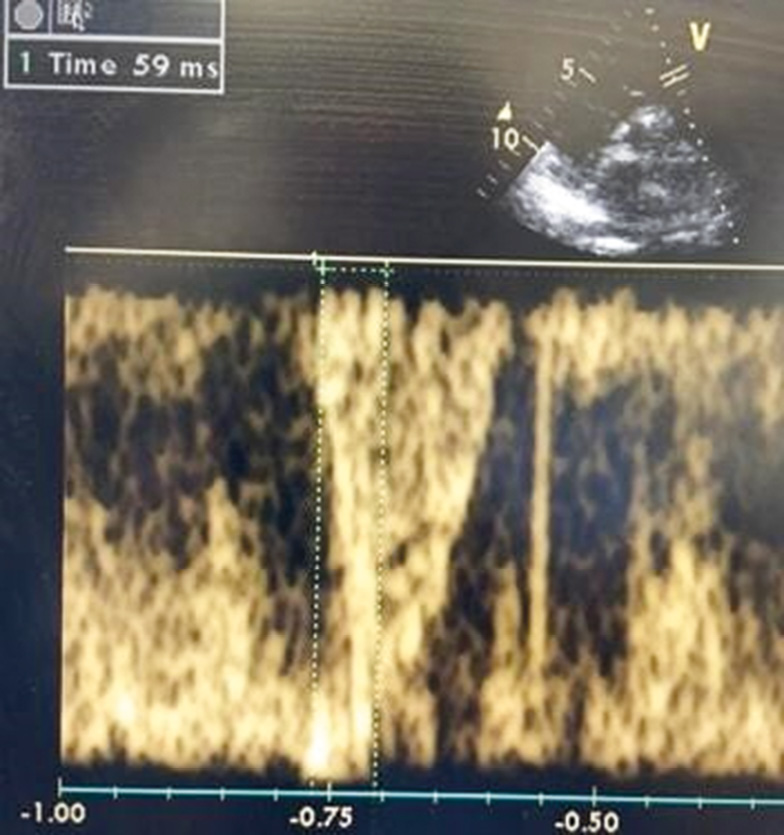

Среднее давление в легочной артерии определяли по времени ускорения потока в выносящем тракте правого желудочка, как показано на рис. 1. Пульсовая волна в выносящем тракте правого желудочка обычно обладает куполообразной формой, но у пациентов с легочной гипертензией наблюдают ее быстрый подъем до пика, что приводит к более короткому времени ускорения [6]. Качество сигнала очень важно, и для повышения точности исследования использована максимальная скорость развертки. Время ускорения в выносящем тракте правого желудочка измеряли от начала потока до его пиковой скорости. Среднее давление в легочной артерии (pЛА) рассчитывали по формуле: pЛА = 90 − 0,62t, где t — время ускорения потока в выводном отделе правого желудочка (рис. 1). При наличии трикуспидальной регургитации среднее давление в легочной артерии определяли по интегралу скорости и времени регургитации. Затем добавляли давление в правом предсердии для расчета среднего давления в легочной артерии. Среднее легочное давление, измеренное этим методом, тесно коррелирует с измеренным инвазивно катетером [6]. Среднее давление в легочной артерии на основе интеграла времени и потока трикуспидальной регургитации рассчитывали по следующей формуле: рЛА = ΔP + рПП, где ΔP — средний градиент трикуспидальной регургитации; рПП — давление в правом предсердии.

Рис. 1. Измерение времени ускорения потока в выносящем тракте правого желудочка